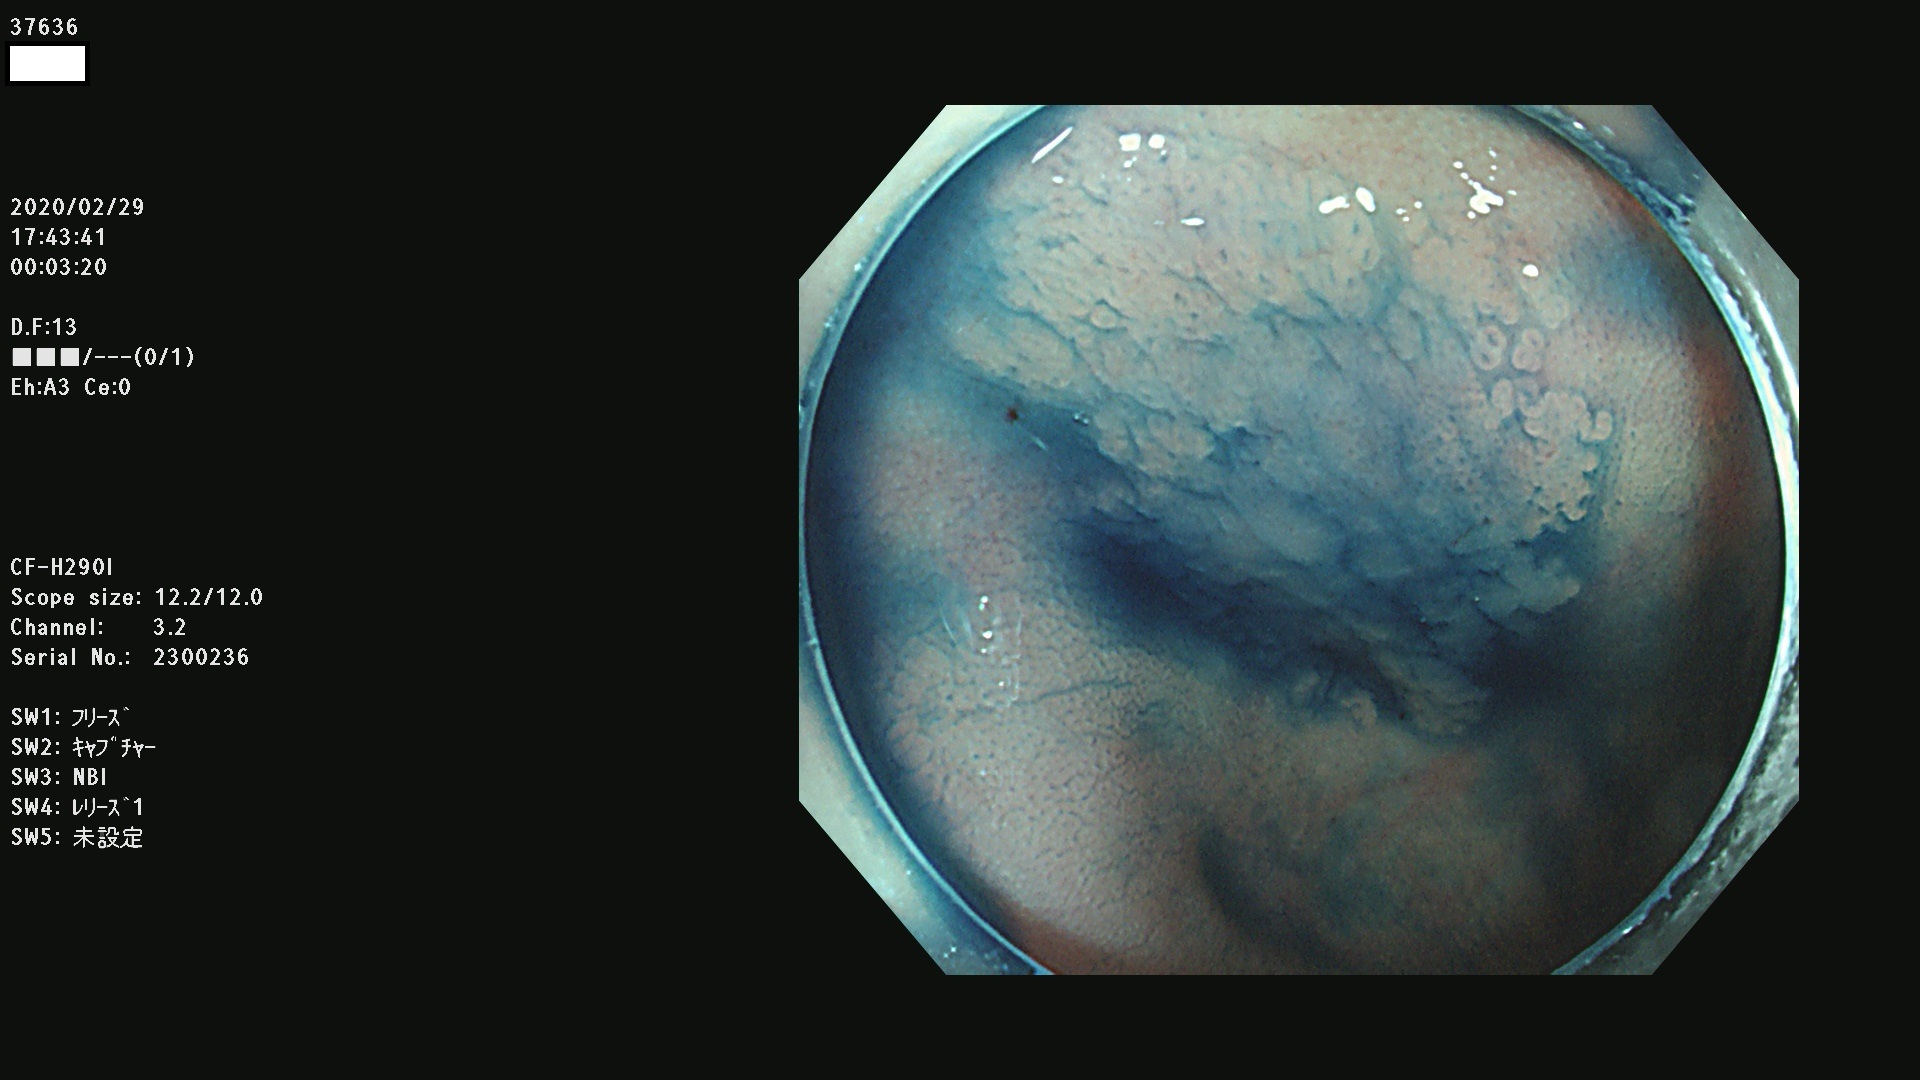

37600 37601 37602 37603 37604 37605 37606 37607 37608 37612 37614 37616 37618 37619 37620 37621 37622(SSAPのみ) 37623(SSAPのみ) 37624 37626 37627 37628 37629 37632 37633 37635 37636(SSAPのみ) 37639 37640 37641 37642 37643 37644 37647(SSAPのみ) 37648 37649 37650 37652 37653 37655 37657 37659 37660 37662 37664 37666 37668(SSAPのみ) 37670 37671 37672 37676 37677 37678 37679 37680 37682 37684 37685(SSAPのみ) 37686 37687 37688 37689 37690 37691 37692(SSAPのみ) 37693 37694 37695 37696 37697 37699

発見困難で危険性の高い平坦型病変(上記100名より抽出)